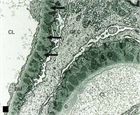

1. 糸球体毛細血管係蹄の上皮側に免疫複合体が沈着して発症し進展する糸球体障害で、非選択性の大量タンパク尿を呈する。確定診断は腎生検による。